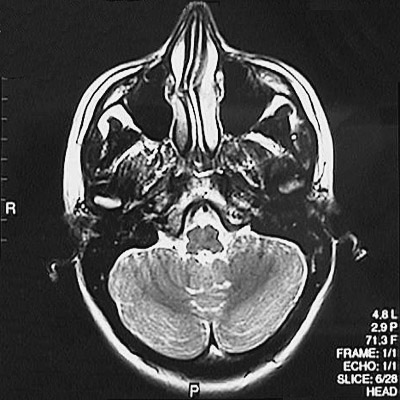

This is a normal axial T2 weighted MRI scan demonstrating the nasal septum and concha and maxillary sinus and sphenoid sinus and medulla and fourth ventricle and cerebellar hemisphere.